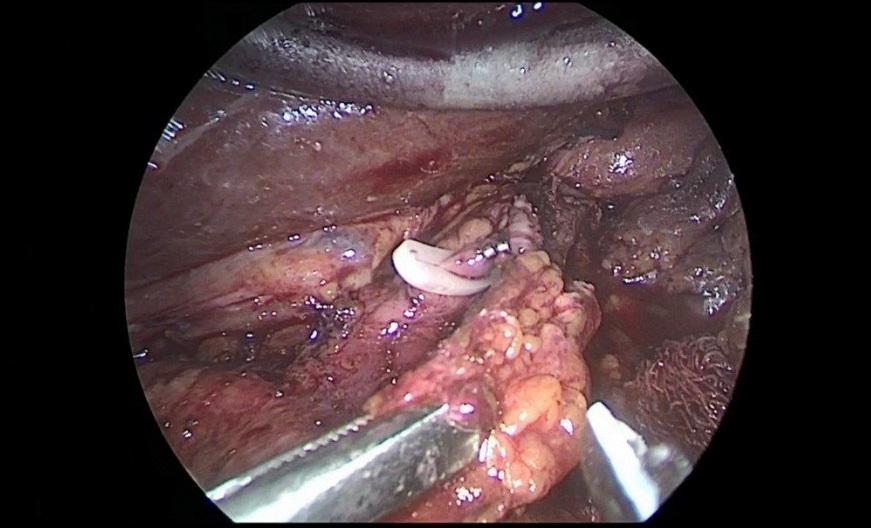

After crossing the pyloric sphincter, laparoscopic lymph node dissection of the VII, VIIIa, IX, XI, XIIa groups of lymph nodes was performed (Figure 9 a, b, c, d).

Figure 9a,b,c,d: Lymph node dissection of the hilum of the liver and celiac trunk.